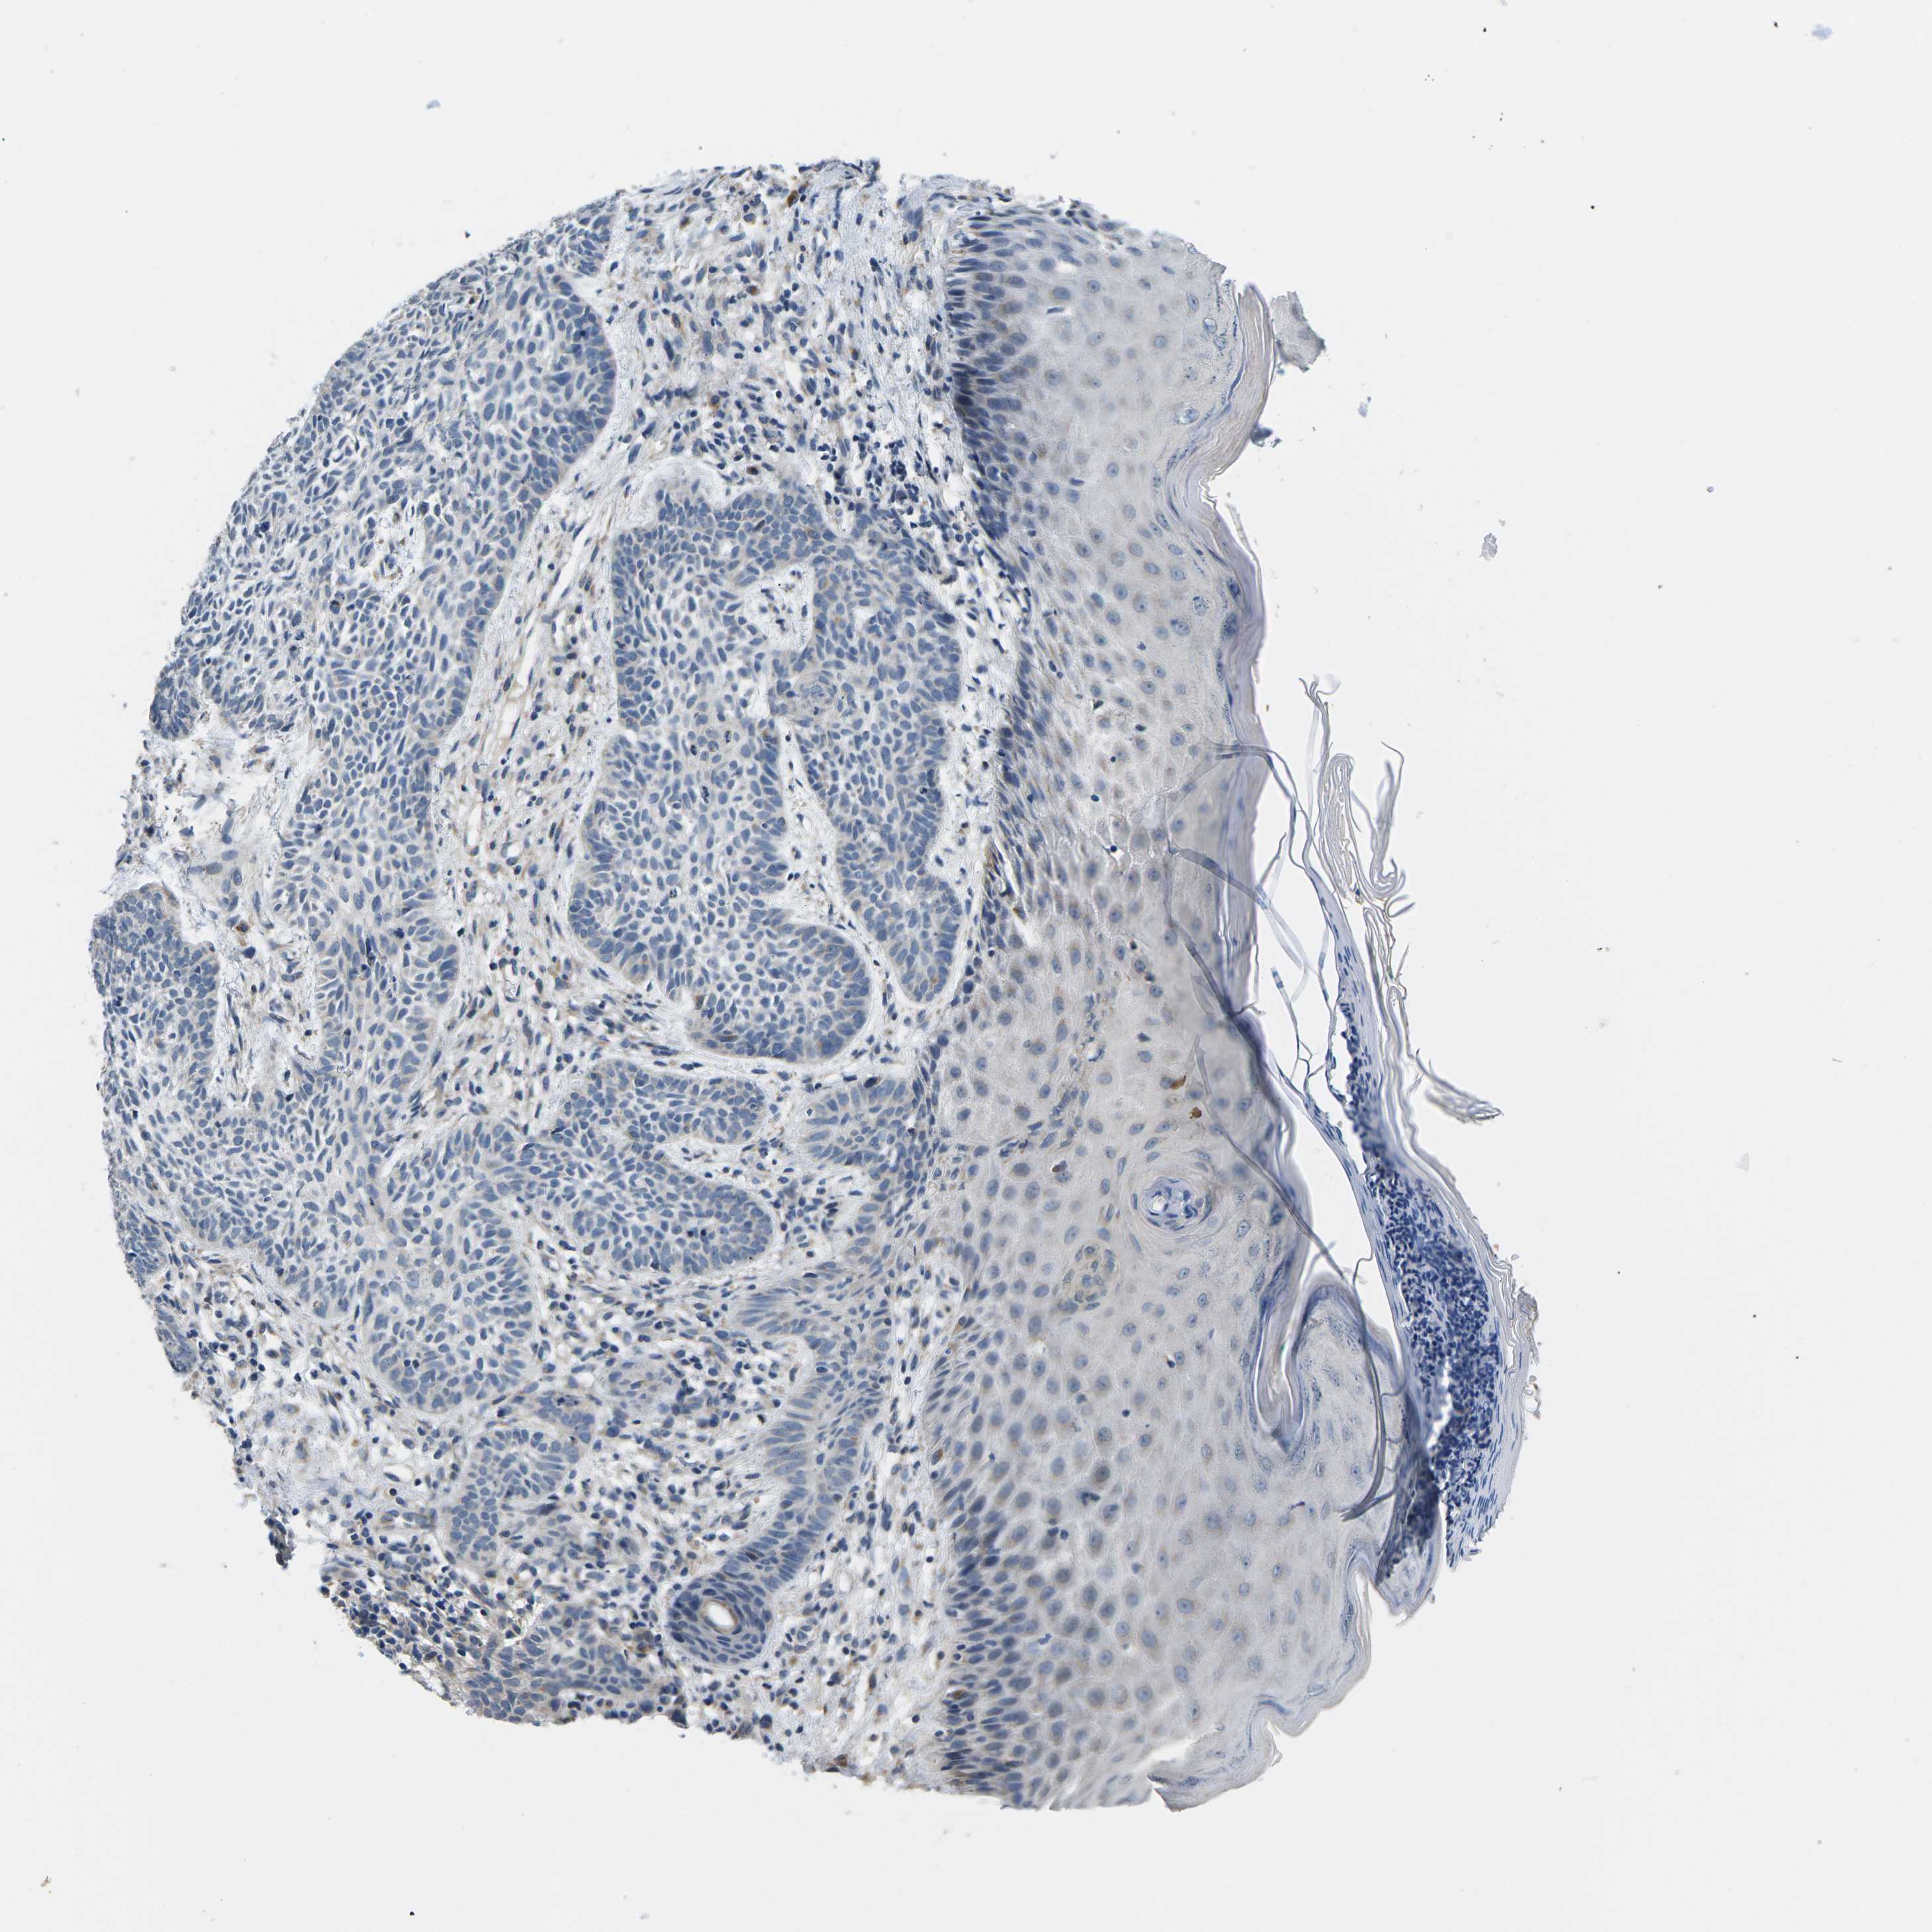

SKIN CANCER - Protein expressioni

A mouse-over function shows sample information and annotation data. Click on an image to view it in a full screen mode. Samples can be filtered based on level of antibody staining by selecting one or several of the following categories: high, medium, low and not detected. The assay and annotation is described here.

Antibody staining in the annotated cell types in the current human tissue is reported as not detected, low, medium, or high, based on conventional immunohistochemistry profiling in selected tissues. This score is based on the combination of the staining intensity and fraction of stained cells.

Each image is clickable and will lead to virtual microscopy that enables deeper exploration of all samples and also displays staining intensity scores, fraction scores and subcellular localization as well as patient and tissue information for each sample.

Antibody HPA015968

Squamous cell carcinoma in situ, NOS

Squamous cell carcinoma, NOS

Basal cell carcinoma

Adnexal tumor, benign